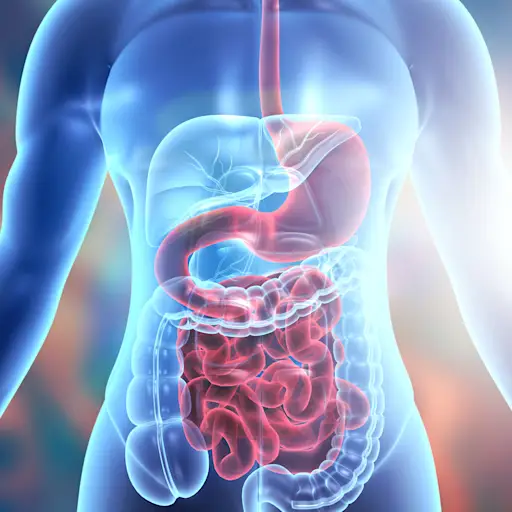

关键区别#1:位置

克罗恩斯和UC之间的一个主要区别是受影响的消化道的一部分。首先,快速回顾消化系统的解剖结构:您的胃肠道(GI)道由口腔,食道,胃,小肠(也称为小肠),大肠(也称为结肠或大肠),包括口腔,食管,胃,小肠)组成。直肠和肛门。Chowdhury博士解释说:“克罗恩病可能会影响胃肠道的任何部分,而UC仅涉及结肠。”克罗恩斯和结肠炎基金会说,尽管克罗恩的可能影响更多的潜在领域,但它通常会影响小肠的末端(卵巢)。